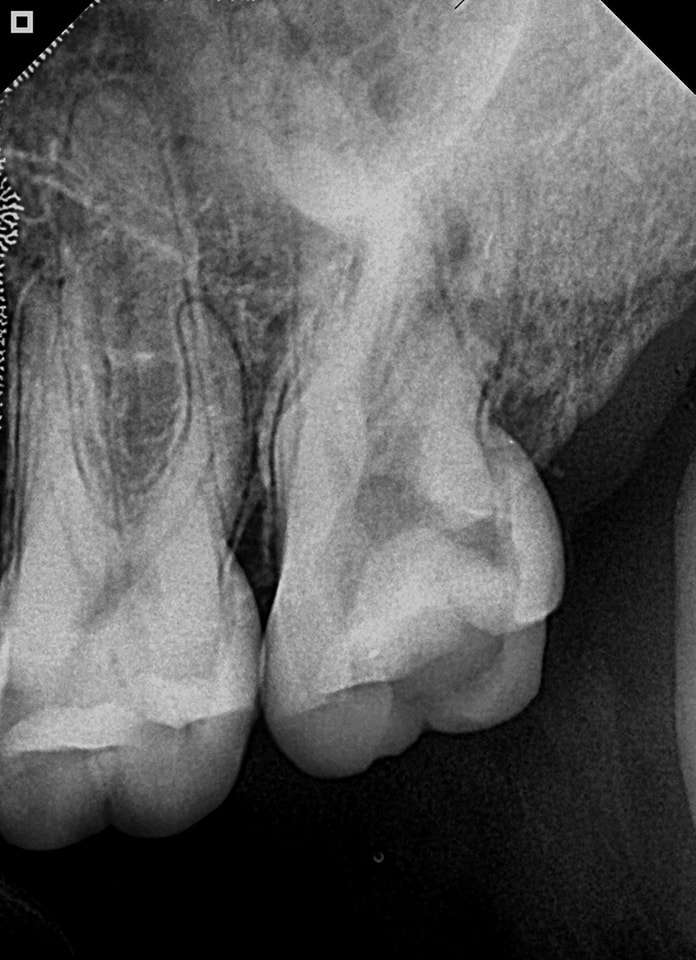

Pre-op